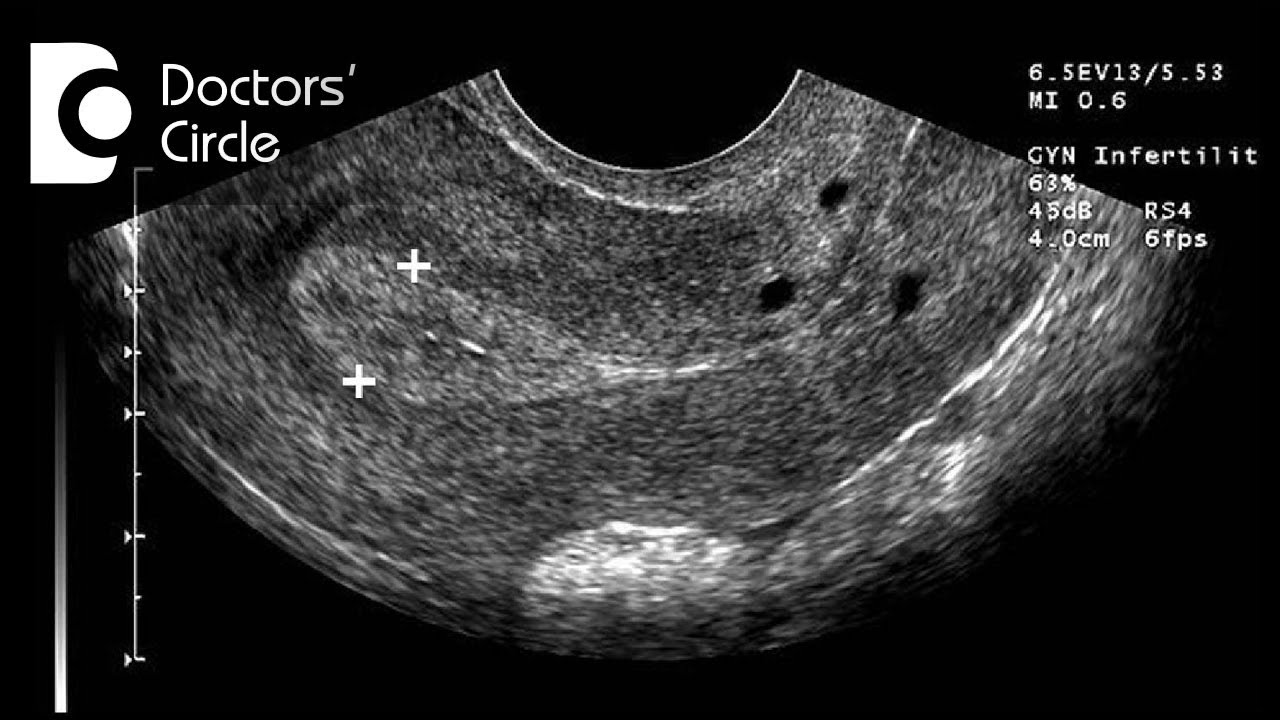

Endometrial Thickness Radiology Reference Article .

Endometrial Thickness Radiology Reference Article .

Endometrial Thickness What Is Normal And How To Measure .

Endometrial Thickness Radiology Reference Article .

Sonohysterographic Measurement Of Endometrial Thickness .